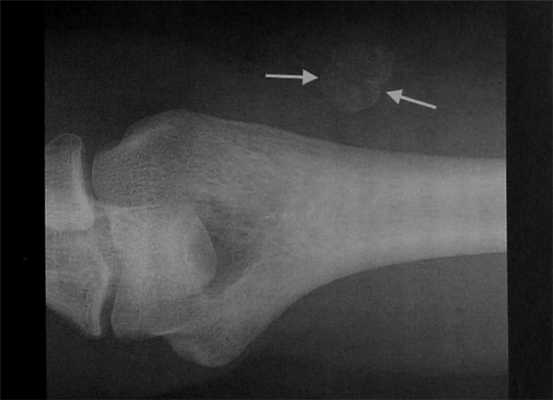

Мужчина 29 лет с болевым синдромом в верхних отделах правого плеча и наличием затруднений при разгибании в плечевом суставе в течение 2 мес. Отсутствие травмы в анамнезе. Рентгенография локтевого сустава. Четко ограниченный, с гладким краем округлый участок окостенения в мягких тканях латеральнее дистального отдела плечевой кости. Оссифицирующий миозит, подтвержденный при рентгенологическом исследовании.